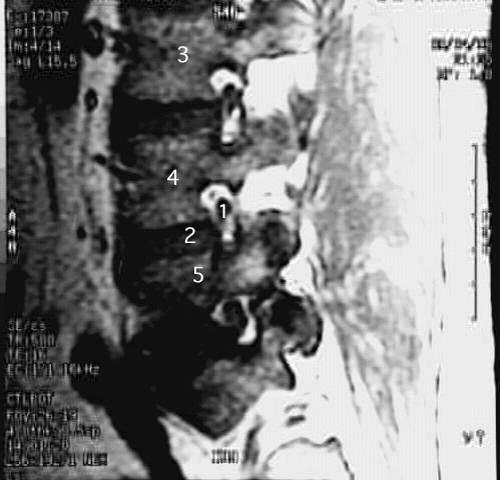

Back- Lumbar Spine Zoom 2

1. Spinal nerve in intervertebral foramen

2. Intervertebral disc

3. Body of the 3rd lumbar vertebra

4. Body of the 4th lumbar vertebra

5. Body of the 5th lumbar vertebra